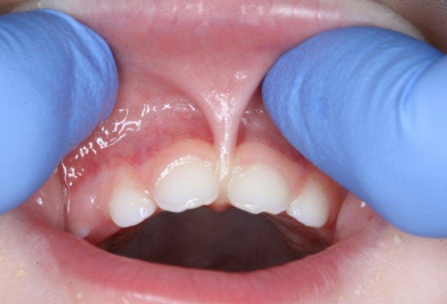

Hallo moms, sudah pernah dengar istilah lip tie? Lip tie adalah keadaan dimana selaput jaringan otot yang menghubungkan bibir atas ke gusi bagian atas, yang disebut frenulum, terlalu membatasi mobilitas mulut, karena terlalu tebal, terlalu ketat, atau keduanya. Tampilan klinis lip tie seperti yang ditunjukkan pada gambar di bawah ini:

Terdapat 4 klasifikasi lip tie berdasarkan tingkat keparahannya, yaitu sebagai berikut:

Tipe 1: frenulum tipis dan tidak begitu terlihat sehingga tidak mengganggu dan tidak diperlukan treatment khusus.

Tipe 2: frenulum melekat pada sebagian besar area gusi. Pada umumnya tidak mengganggu atau menimbilkan keluhan.

Tipe 3: frenulum terdapat di area gusi ditempat dimana gigi depan depan atas akan terbentuk. Sulit menggerakkan bibir dan meningkatnya resiko karies pada gigi depan atas.

Tipe 4: frenulum meluas hingga langit-langit mulut. Biasanya bibir atas menutupi sebagian atau keseluruhan gigi depan, meningkatnya resiko karies pada gigi depan atas.

Keadaan yang termasuk lip tie adalah tipe 3 dan 4.